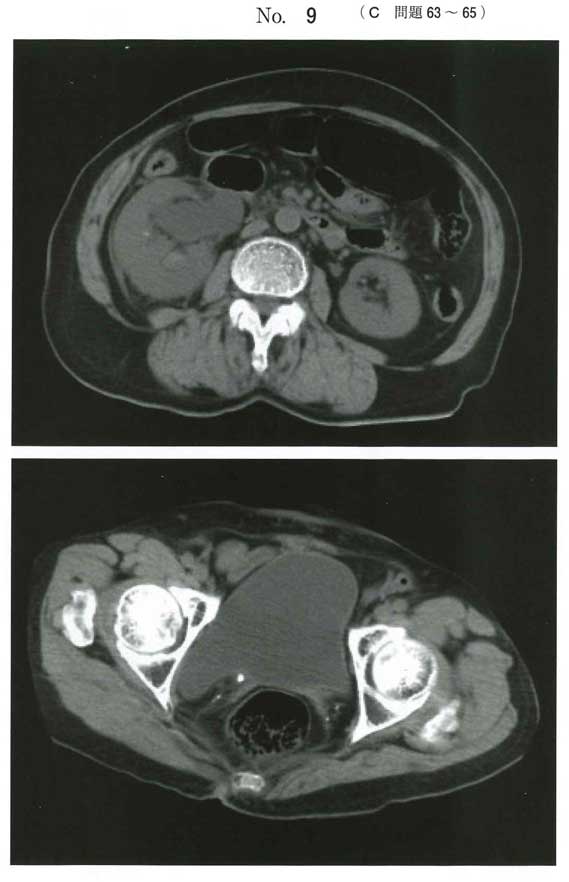

dです。泌尿器科医です。右尿管結石による閉塞性腎盂腎炎です。qSOFA 2点にて敗血症を疑います。細胞外液の投与、血液培養採取後に抗菌薬投与、その後可及的速やかに尿管ステント留置です。